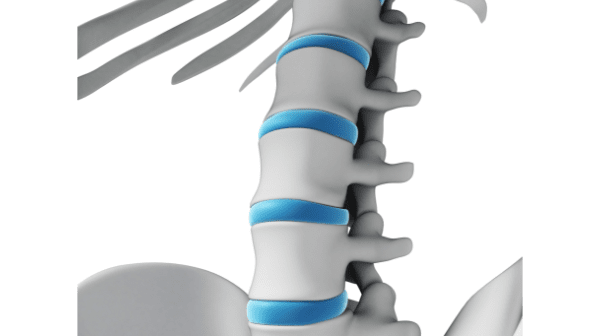

정상